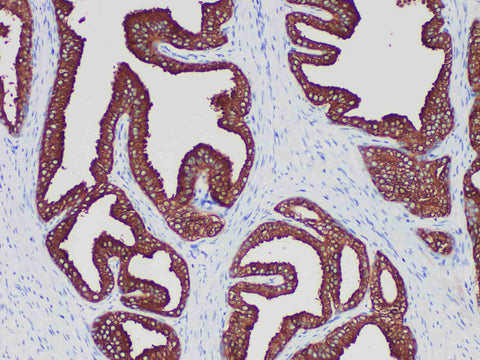

PSA Monoclonal Antibody Stored at -20°C

| Applications | IHC-P |

| Cellular Localization | Cytoplasm |

| Tissue Specificity | prostatic cancer |

PSA is a kind of glycoprotein synthesized by prostatic epithelial cells. At present, it is considered to be one of the specific tumor markers, which is mainly used in the judging of prostate cancer and metastatic prostate cancer, but it can not be used as the differential judging of benign and malignant prostate diseases. Because, the vast majority of prostatic hyperplasia epithelium are positive.